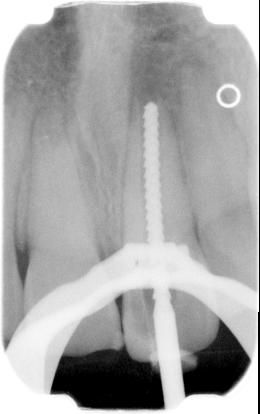

Deze worden ingesteld op een lengte zodanig dat niet voorbij de apex kan worden geboord. Vervolgens wordt met een licht schrapende beweging de kanaalwand aan alle kanten gereinigd. Bij alle methoden is de behandelmicroscoop onontbeerlijk om het resultaat te beoordelen. Nu wordt MTA (Pro Root) aangemaakt en het apicale deel van het kanaal (plus minus 5 mm) wordt hiermee gevuld. Een nat watje wordt op het aangebrachte MTA (Pro Root) geplaatst. Dit moet minstens 4 uur uitharden, daarom is een derde zittig nodig.

laatste xf is een controlefoto 1 jaar na de behandeling

In de derde zitting wordt het watje verwijderd en de rest van het kanaal gevuld zoals gebruikelijk.